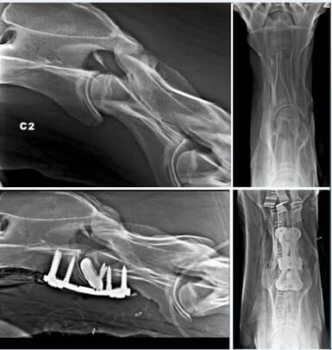

Während der Operation wird das Pferd anästhesiert und in einer chirurgischen Hängematte immobilisiert. Eine mit dem 3D-Drucker hergestellte Platte und 3D-gedruckte Spongiosaschrauben stabilisieren den Bruch und überbrücken die Wirbel. Abhängig von den betroffenen Wirbeln wird im ventralen Bandscheibenbereich ein kleiner 3D-gedruckter Cage aus Titan eingesetzt.

Zur Kompression des gebrochenen Fragments wird manchmal eine Kombination aus Spongiosa- oder Kortikal- und Verriegelungsschrauben verwendet. Dadurch kann ein mit 3D-Druck hergestellter Bandscheiben-Spacer aus Titan mit seiner Kompressionskraft den Abstand zwischen den Wirbeln aufrechterhalten. Das verhindert, dass die Bandscheibe in den Markkanal ragt und der kaudale Wirbel sich ventral verschiebt.

Die Form der Platte ermöglicht die Platzierung der drei Schrauben in jedem Wirbel. Titan-Implantate ermöglichen eine bessere Osseointegration als Stahlimplantate. Mit dem Metall-3D-Druck können poröse Strukturen angefertigt werden, die das durch den Cage hindurch und die Fixierung des Knochens am Cage erleichtern.

Bisher sind bei diesem Eingriff, der unter Röntgen- oder Durchleuchtungskontrolle durchgeführt wird, nur wenig Komplikationen aufgetreten, wie die Bildung von Seromen oder das Lösen von Schrauben. Diese Methode ist bei zervikaler Arthrodese oder im Fall eines Traumas geeignet, aber auch bei Fehlstellungen.